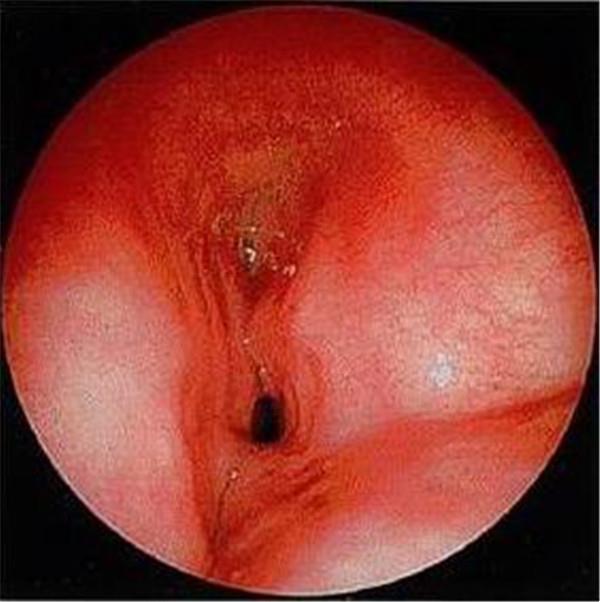

檢查中氣道內(nèi)情景